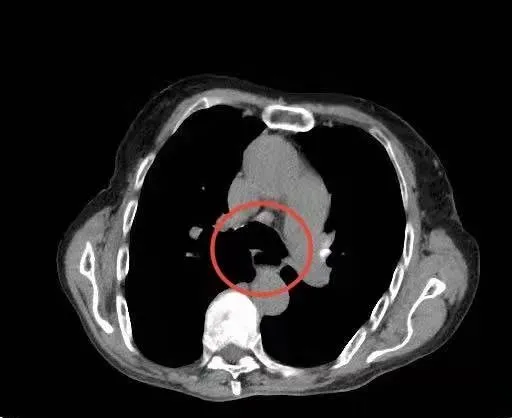

看到這個老人家,身體基礎還不錯,氣色不錯,無有貧血,看起來不像八十多歲的老人呢?為什麼會出現上述症狀呢?常玉英主任隨即為她完善了相關檢查,排查了心臟病、肺部疾病等。但患者胸部CT發現,食管中上段管腔擴張,在中下段似有腫物生長。醫生護士們面露難色,難道又有一個腫瘤患者?

△胸部CT影像圖顯示患者食管中上段管腔明顯擴張